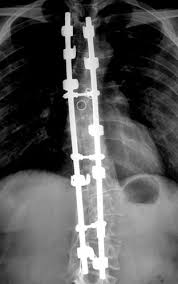

Spine Surgery Cost In India Spine Surgery Surgery Spinal Fusion Surgery

Spine Surgery Cost In India Spine Surgery Surgery Spinal Fusion Surgery from in.pinterest.com